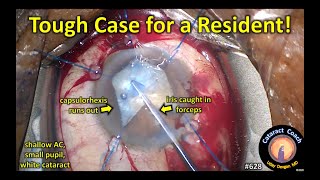

CataractCoach 1203: resident surgeon's 200th cataract surgery Tough cataract surgery case for a resident!

Tough cataract surgery case for a resident! resident cataract case #165 -- what needs improvement?

CataractCoach 1203: resident surgeon's 200th cataract surgery Tough cataract surgery case for a resident!

Tough cataract surgery case for a resident! resident cataract case #165 -- what needs improvement?